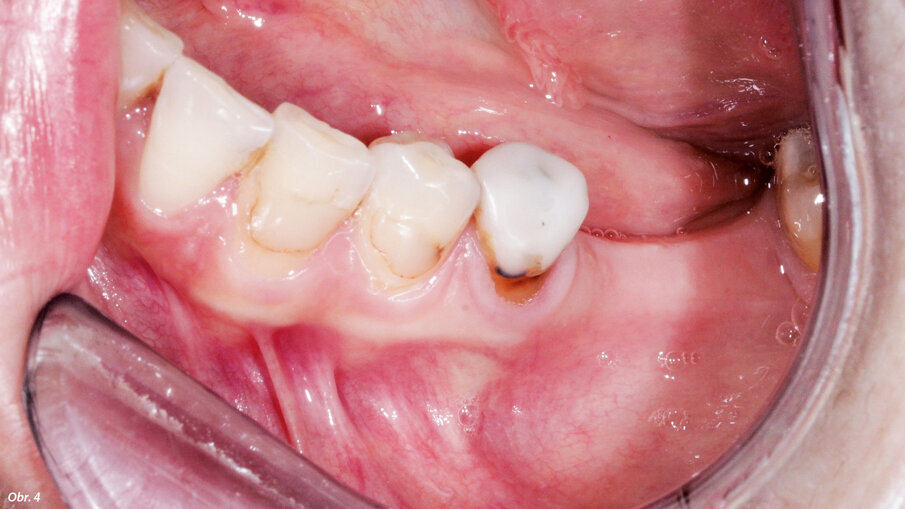

Na ošetření se dostavil 36letý pacient s chybějícími zuby 36 a 37 a horizontálním defektem kosti ve stávající mezeře. Bylo by sice bývalo možné zavést implantáty, ale zůstala by pouze tenká vrstva vestibulární kosti při krčcích implantátů. Hrozilo tedy vážné riziko dehiscence, která může ohrozit zachování implantátu v oblouku (obr. 4).